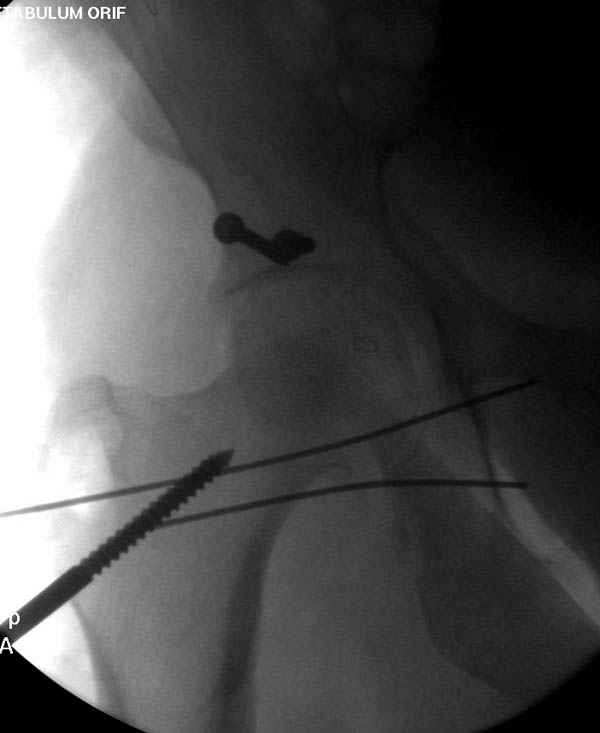

По снимку создается впечатление о высоком поперечном переломе, задней колонны, стенки; почему не пользовались *magic screw*?

Латеральное положение облегчает проведение тракции через вертел, за 5 мм стержень за вертел (грузом через тракционное приспособление), на обычном рентгенопрозрачном операционном столе, а для положения на животе, наверное, Judet Table более приемлем, потому что там имеется латеральное тракционное устроиство.

Там множество обычных 2.7 мм шурупов, потом идет фиксация основными пластинами.

Снимки здесь....